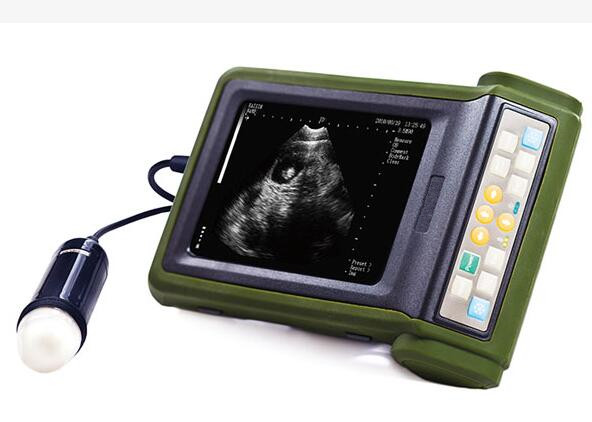

Product name : Mobile Ultrasound Scanner

Monitor size : 5.7" High resolution color LED

Animal Handheld Full Digital Ultrasound Scanner Small Ultrasound Machine Only 1.1Kg Weight

Advantage for Mini Ultrasound Machine

| 3 | 5.7" High resolution color LED |

Image for Mobile Ultrasound Machine

Hand Held Animal Full Digital Ultrasound Scanner Small Ultrasound Machine LightWeight Images |